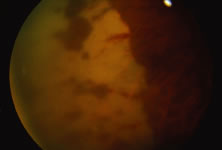

The ARN patient typically presents with progressive visual blurring in one or both eyes occurring over several weeks. These patients often are initially treated with corticosteroids, antitoxoplasmosis drugs, and other medications before arriving at the correct diagnosis. Examination reveals a prominent anterior uveitis that may be granulomatous or nongranulomatous (Fig. 1). Inflammatory signs may be prominent and cause severe pain (Fig. 2). The uveitis may be diffuse and so severe that it causes proptosis. These signs, and the diffuse vitreitis that makes the view of the retina difficult, may contribute to the high degree of delayed and/or misdiagnosis that occurs in the early stages of the disease. Significant vitreous cellular infiltration is seen in the presence of retinitis that is manifest by opacification of the retina, often most prominently in the periphery. Posterior pole involvement may include retinitis, as well as inflammation of the optic nerve head. Optic neuropathy might be the first sign of ARN with subsequent development of other retinal manifestations.8 Ultrasonography and computed tomography (CT) might be helpful in cases of ARN associated with optic nerve edema revealing enlargement of the optic nerve sheath.9 Even in ARN patients who are not immunocompromised and who have no clinical evidence of encephalitis, magnetic resonance imaging of selected cases has shown lesions of the lateral geniculate, optic tracts, and chiasma, which suggests that the virus spreads through the central nervous system (CNS) by axoplasmic transport from the retinal ganglion cells.10 A secondary retinal vasculitis is common, often accompanied by a mild number of retinal hemorrhages. Days to weeks after onset of the infection, the discrete peripheral lesions typically coalesce into a white or yellow ring of infected retina, and the associated vasculature is obliterated (Fig. 3). Necrotic retina desquamates into the vitreous resulting in vitreous sheets.3,6 Eventually, most untreated eyes can be expected to develop retinal detachment resulting from development of multiple full-thickness retinal breaks accompanied by traction or exudation.11 Giant retinal pigment epithelial tears have also been reported.12